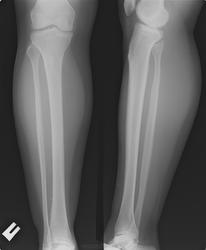

Кальцинаты в мягких тканях голени  по передней поверхности, за счёт чего?

может давняя оссифицированная гематома

Флеболит

Наверное, флеболит(ы) - выше ещё несколько маленьких есть.) А лимфолит быть не может таким - нехарактерным? А сосудистые "звёздочки" - гемангиомы у пациента немолодого - не бывает такого?)

Никакого практического значения не имеют. А значит - "забавлялка". Откуда и почему? Случайная находка оссификатов в мягких тканях,  причин:  отсюда - до бухты Ванино. По поводу флеболитов - это же не малый таз, какие такие вены по передней поверхности голени, чтоб флеболиты?.

Коллега, Вы чего? Вены - это которые с клапанами, которые ещё образуют узлы варикозные, в которых кровь надолго задерживается, слёживаясь в флеболиты однажды...

Если бы у всех было всё одинако, мы не нашли бы работу. Анатомия - о том, как бывает, как быть должно, но у вен веточек столько же, сколько вариантов строения лёгочных сосудов. А мелкие венулы если на схеме дорисовать, то будет паника у кого-то от их обилия и вариантов строения.